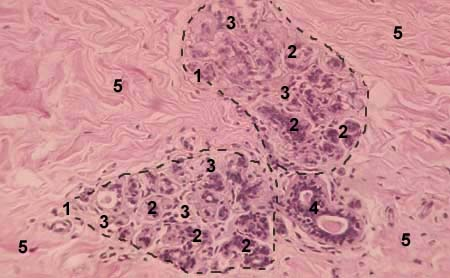

Рисунок 3- Нелактирующая молочная железа

1-дольки железы; 2- зачатки концевых секреторных отделов; 3-внутридольковая соединительная ткань; 4- междольковый выводной проток; 5- междольковая соединительная ткань